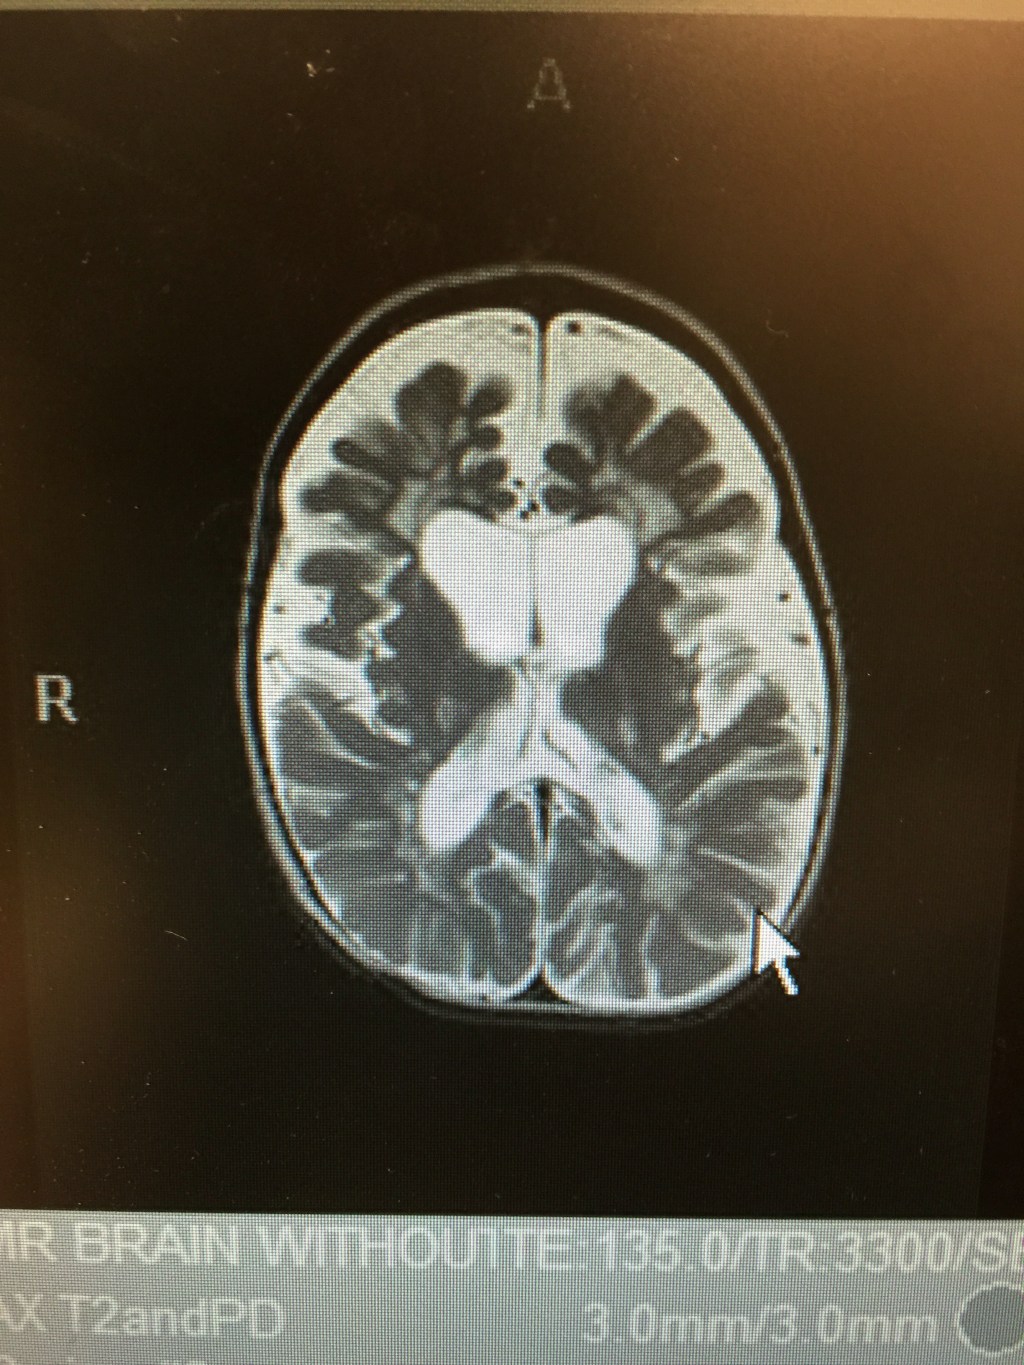

She also showed us an image of Tori’s current MRI so we could compare it to the one from last year:

Unfortunately, her brain has continued to atrophy and Krabbe is still very present. But, God is sovereign and still in control!